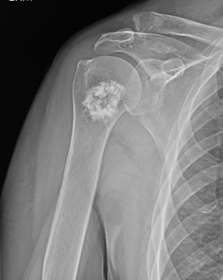

X-rays. Cartilage lesions can often be identified by their radiographic appearance (how they look on an X-ray).

On X-ray:

• Chondrosarcomas have a more aggressive radiographic appearance. The X-ray will show destruction of bone, a large soft tissue mass, and possibly a fracture.

X-ray of Chondrosarcoma

Aggressive-appearing cartilage tumor with bony destruction and soft-tissue mass most consistent with chondrosarcoma.